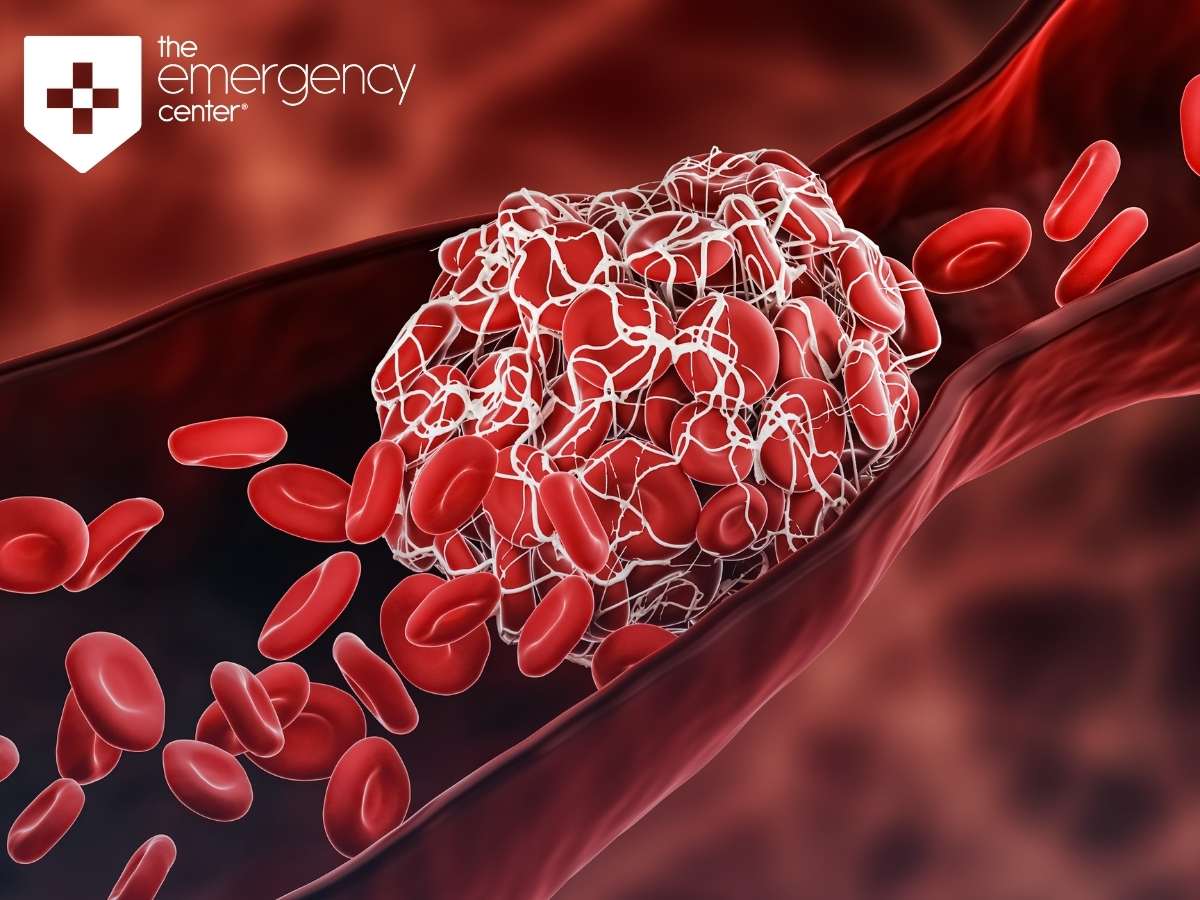

:max_bytes(150000):strip_icc()/overview-blood-clots-1745326_final-3990f6d12e19428e8734d92f068ce0de.png)

:max_bytes(150000):strip_icc()/overview-blood-clots-1745326_final-3990f6d12e19428e8734d92f068ce0de.png)